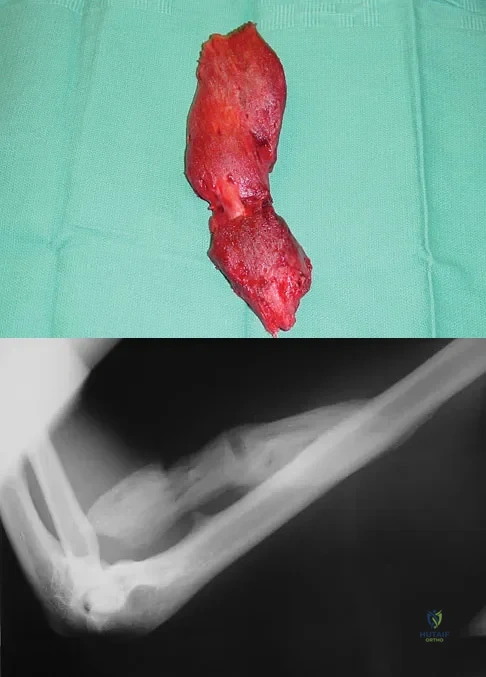

A 43-year-old woman has had pain in the left hip for the past 2 months. A radiograph, CT scan, MRI scan, and biopsy specimens are shown in Figures 16a through 16e. What is the most likely diagnosis?

A 13-year-old girl was riding on an all-terrain vehicle when the driver struck a tree. She sustained the injury shown in Figures 45a through 45d. This injury is best described as what type of acetabular fracture pattern?

Explanation